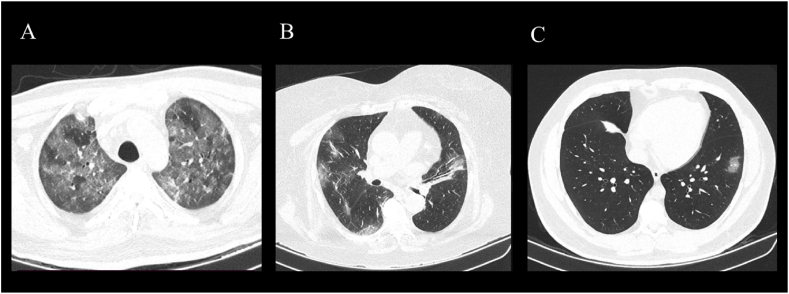

The following criteria were used to classify pneumonia as severe: 1) respiratory distress, ventilatory rate >30 breaths/min; 2) at rest, finger-clip oxygen saturation <93%; and 3) PaO2/FIO2<300 mmHg. While critical pneumonia was defined by the following criteria: 1) respiratory failure requiring mechanical ventilation; 2) shock; and 3) other organ failures requiring Intensive Care Unit (ICU) monitoring [11]. Imaging classification was performed by two independent radiologists (Cohen's kappa = 0.89), and diagnostic and classification discrepancies were resolved via a third party and a consensus between the three radiologists. The blinded radiological classification initially dichotomized the CT scans as suggestive of COVID-19 or not suggestive of COVID-19. The tomographic findings were classified as 1) consolidation pattern, 2) ground-glass pattern, 3) nodular pattern, 4) presence of ganglia, 5) presence of thrombosis, and 6) vascular thickening pattern (Fig. 1). Furthermore, pattern and lesion location were recorded (i.e., right, left, or bilateral lung involvement, peripheral distribution, or basal distribution). A pulmonary damage severity index was calculated based on the estimated percentage of lung involvement based on the following criteria: a) score 0, 0% involvement; b) score 1, less than5% involvement; c) score 2, 5%–25% involvement; d) score 3, 26%–49% involvement; e) score 4, 50%–75% involvement; and f) score 5, greater than 75% involvement [13,14]. Each lobe was scored using these criteria, thus a total possible score of 0–25 was obtained for each patient at the time of ICU admission (i.e., <24hrs after positive PCR test for SARS-CoV-2).

Fig. 1.

Tomographic findings

A) Computed tomography, axial cut of the lung. Severe affection of the lung, both superior lung lobules are seen with a diffuse ground-glass image with air entrapment. Interlobular septal thickening, as well as vascular thickening pattern. B) Computed tomography, axial cut of the lung. Moderate affection of the lung, ground-glass zones with subpleural distribution are observed, with interlobular septal thickening and vascular thickening. C) Computed tomography, axial cut of the lung. Mild affection of the lung, small ground-glass opacities in the lower left lobule are observed.